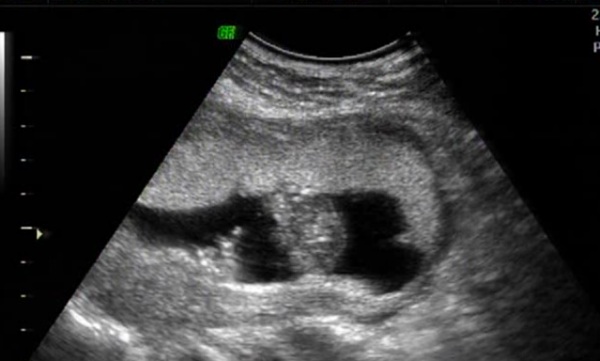

Those are terrible images, I can't even tell they're potty shots. I don't see any gender clues at all. Did the tech say anything?

He leaned girl but he said b previous daughter is a boy, she is all girl! So can I believe him this time?

Here is my scan video, was not for gender determination, but I cannot find boy bits, trying to find them cause swayed strictly boy with MSU !